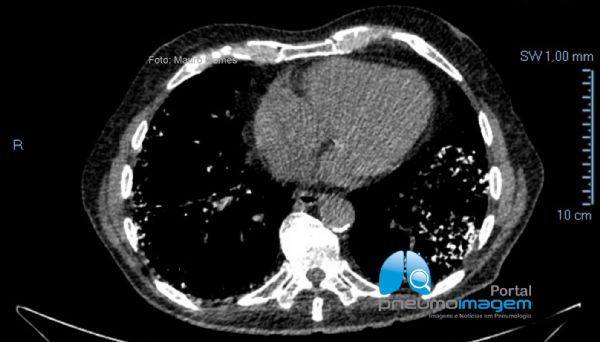

Nesses cortes podem-se observar alterações intersticiais com fibrose caracterizadas por reticulado e bronquiectasias de tração com predomínio periférico e basal. As lesões se estendem desde as regiões apicais (menor intensidade) até as bases (maior intensidade). O padrão é de provável pneumonia intersticial usual (PIU). Observe que se associam às lesões múltiplos focos dendriformes de calcificação, compatível com ossificação pulmonar.

In these sections, interstitial changes with fibrosis characterized by reticulate and traction bronchiectasis with peripheral and basal predominance can be observed. The lesions extend from the apical regions (lower intensity) to the lower lobes (higher intensity). The characteristic pattern is probable usual interstitial pneumonia (PIU). Multiple dendriform foci of calcification are associated with lesions, compatible with pulmonary ossification.

Nos cortes com a janela para o mediastino é possível se observar melhor os focos de calcificação intersticial.

In CT slices with the window to the mediastinum, it is possible to better observe the foci of interstitial calcification.